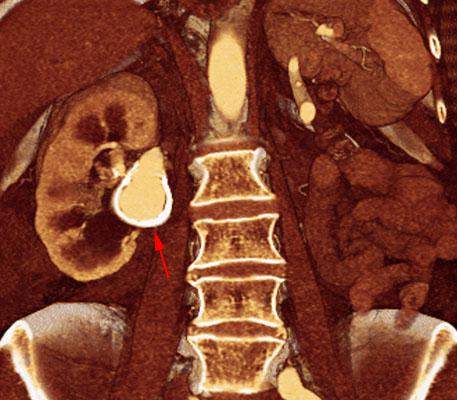

Aneurisma de arteria renal en monorreno

VR seccional. Visión coronal anterior. AngioTC renal mostrando una lesión de pared calcificada, intensamente contrastada en su interior, correspondiente a un aneurisma (flecha)